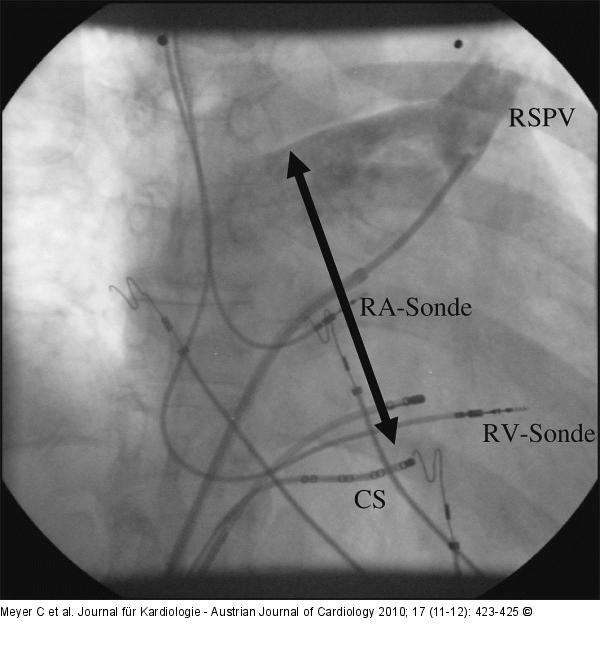

Abbildung 2: Pulmonalvenenangiographie Die späte Phase einer durchgeführten Pulmonalvenenangiographie der rechtssuperioren Pulmonalvene (RSPV) zeigt den deutlich vergrößerten linken Vorhof (Pfeil) der Patientin in einer LAO-60°-Darstellung. RA-Sonde: rechtsatriale Sonde; RV-Sonde: rechtsventrikuläre Sonde des Herzschrittmachers; CS: Koronarsinus. |

Abbildung 2: Pulmonalvenenangiographie

Die späte Phase einer durchgeführten Pulmonalvenenangiographie der rechtssuperioren Pulmonalvene (RSPV) zeigt den deutlich vergrößerten linken Vorhof (Pfeil) der Patientin in einer LAO-60°-Darstellung. RA-Sonde: rechtsatriale Sonde; RV-Sonde: rechtsventrikuläre Sonde des Herzschrittmachers; CS: Koronarsinus. |